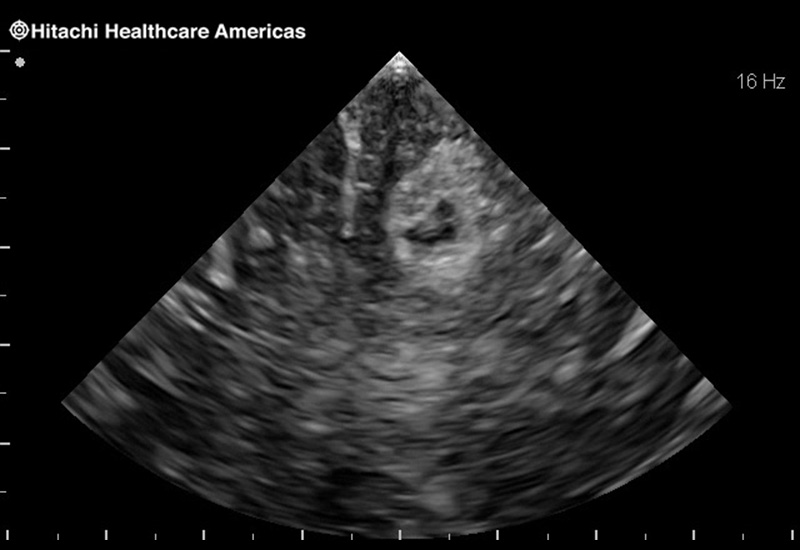

Superior guidance for all applications

Fujifilm Healthcare Americas is committed to designing tools that help surgeons navigate inside the human body and provide the necessary information to immediately make critical surgical decisions.

Fujifilm Healthcare's dedication to Surgeons provides outstanding ultrasound technology, professional support and the specialized tools necessary to best perform comprehensive real-time ultrasound imaging in Breast Surgery, General Surgery, Laparoscopic Surgery, Neurosurgery, Robotic Surgery and Surgical Oncology.

Fujifilm Healthcare’s ARIETTA Precision features state-of-the-art digital architecture and advanced imaging technologies to redefine the capabilities of surgical ultrasound.

Fujifilm Healthcare’s ARIETTA Precision features state-of-the-art digital architecture and advanced imaging technologies to redefine the capabilities of surgical ultrasound.